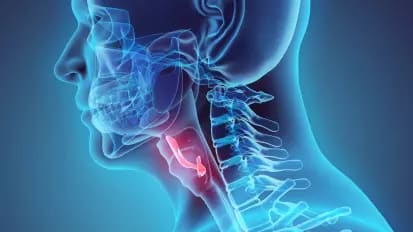

Preserving Laryngeal Structure and Function for Patients with Cancer

Johns Hopkins experts offer innovative surgical techniques that may lessen the damaging impact on the voices of patients with laryngeal cancer.

Research and Clinical Advances in Laryngology at Johns Hopkins

Physician-researchers in the Division of Laryngology advance clinical research and practice — leading studies on retrograde cricopharyngeal dysfunction, gender-affirming voice care and more.